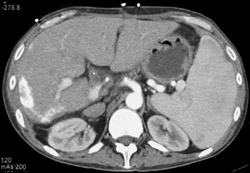

Candidiasis in Liver and Spleen (dual Phase)